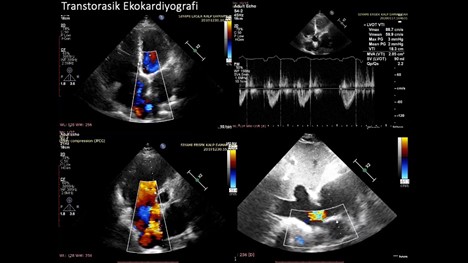

Yapılan transtorasik ekokardiyografisinde; parasternal uzun aks görüntülemede posterior mitral leaflette sütur anuloplastiye baÄŸlı hareket kısıtlılığı, dilate sol atrium görüntülenmekte olup kısa aks görüntülerde sistolde daha belirgin olmak üzere basınç ve volüm yükünü temsil eden “D-shaped” görünüm mevcut. Posterior leafletteki anuloplastiye baÄŸlı hafif mitral darlık fizyolojisi mevcut. Pulmoner arter çapı 38 mm ve dilate. Akselerasyon zamanı kısalmış olarak izlendi (Resim-2).

Resim-2: